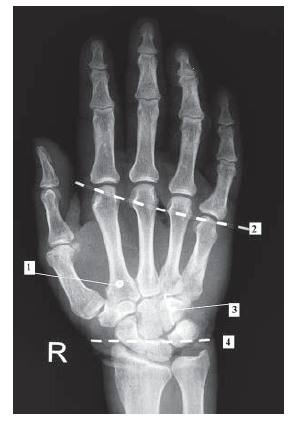

По результатам позиционирования мышечных ворот возвратной двигательной ветви относительно поверхностных и костных ориентиров с учетом 95% доверительного интервала тесная связь нерва с мышцами отмечалась ниже дистальной кожной складки запястья и линии, соединяющей шиловидные отростки лучевой и локтевой костей, на 3,83±1,19 и 4,19±1,43 см соответственно (рис. 2). Относительно поперечной складки ладони мышечные ворота двигательной ветви к мышцам возвышения I пальца располагались проксимальнее на 4,22±1,16 см. Между значениями длины кисти и расстоянием до мышечных ворот относительно линии, соединяющей шиловидные отростки лучевой и локтевой костей, была выявлена выраженная корреляционная зависимость (r=0,71). Зависимость от длины кисти расстояния до мышечных ворот относительно кожной дистальной складки запястья была менее выраженной (r=0,53). Корреляционной связи между величинами расстояния от мышечных ворот до поперечной ладонной складки и значениями длины кисти не обнаружено. Данный факт, по всей вероятности, объясняется изменениями длины кисти за счет изменений длины фаланг пальцев в большей степени, чем за счет изменений длины пястных костей.

Рис. 2. Рентгенограмма кисти с проекциями поверхностных ориентиров и контрастными метками в области нервных ветвей: 1 – мышечные ворота возвратной двигательной ветви срединного нерва, 2 – контрастная метка фиксирована на поперечной складке ладони, 3 – уровень отхождения глубокой ветви локтевого нерва, 4 – контрастная метка на дистальной складке запястья